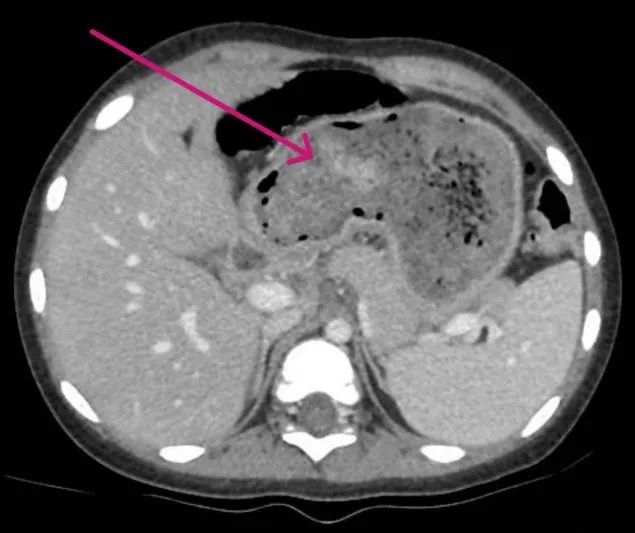

Qua thăm khám và chụp CT-scan, các bác sĩ phát hiện một búi tóc chiếm gần như toàn bộ dạ dày và kéo dài qua tá tràng xuống ruột non. Đây là biểu hiện điển hình của trichobezoar (búi tóc trong dạ dày) tiến triển thành hội chứng Rapunzel. Em A. được chỉ định phẫu thuật mở dạ dày để lấy búi tóc ra ngoài.